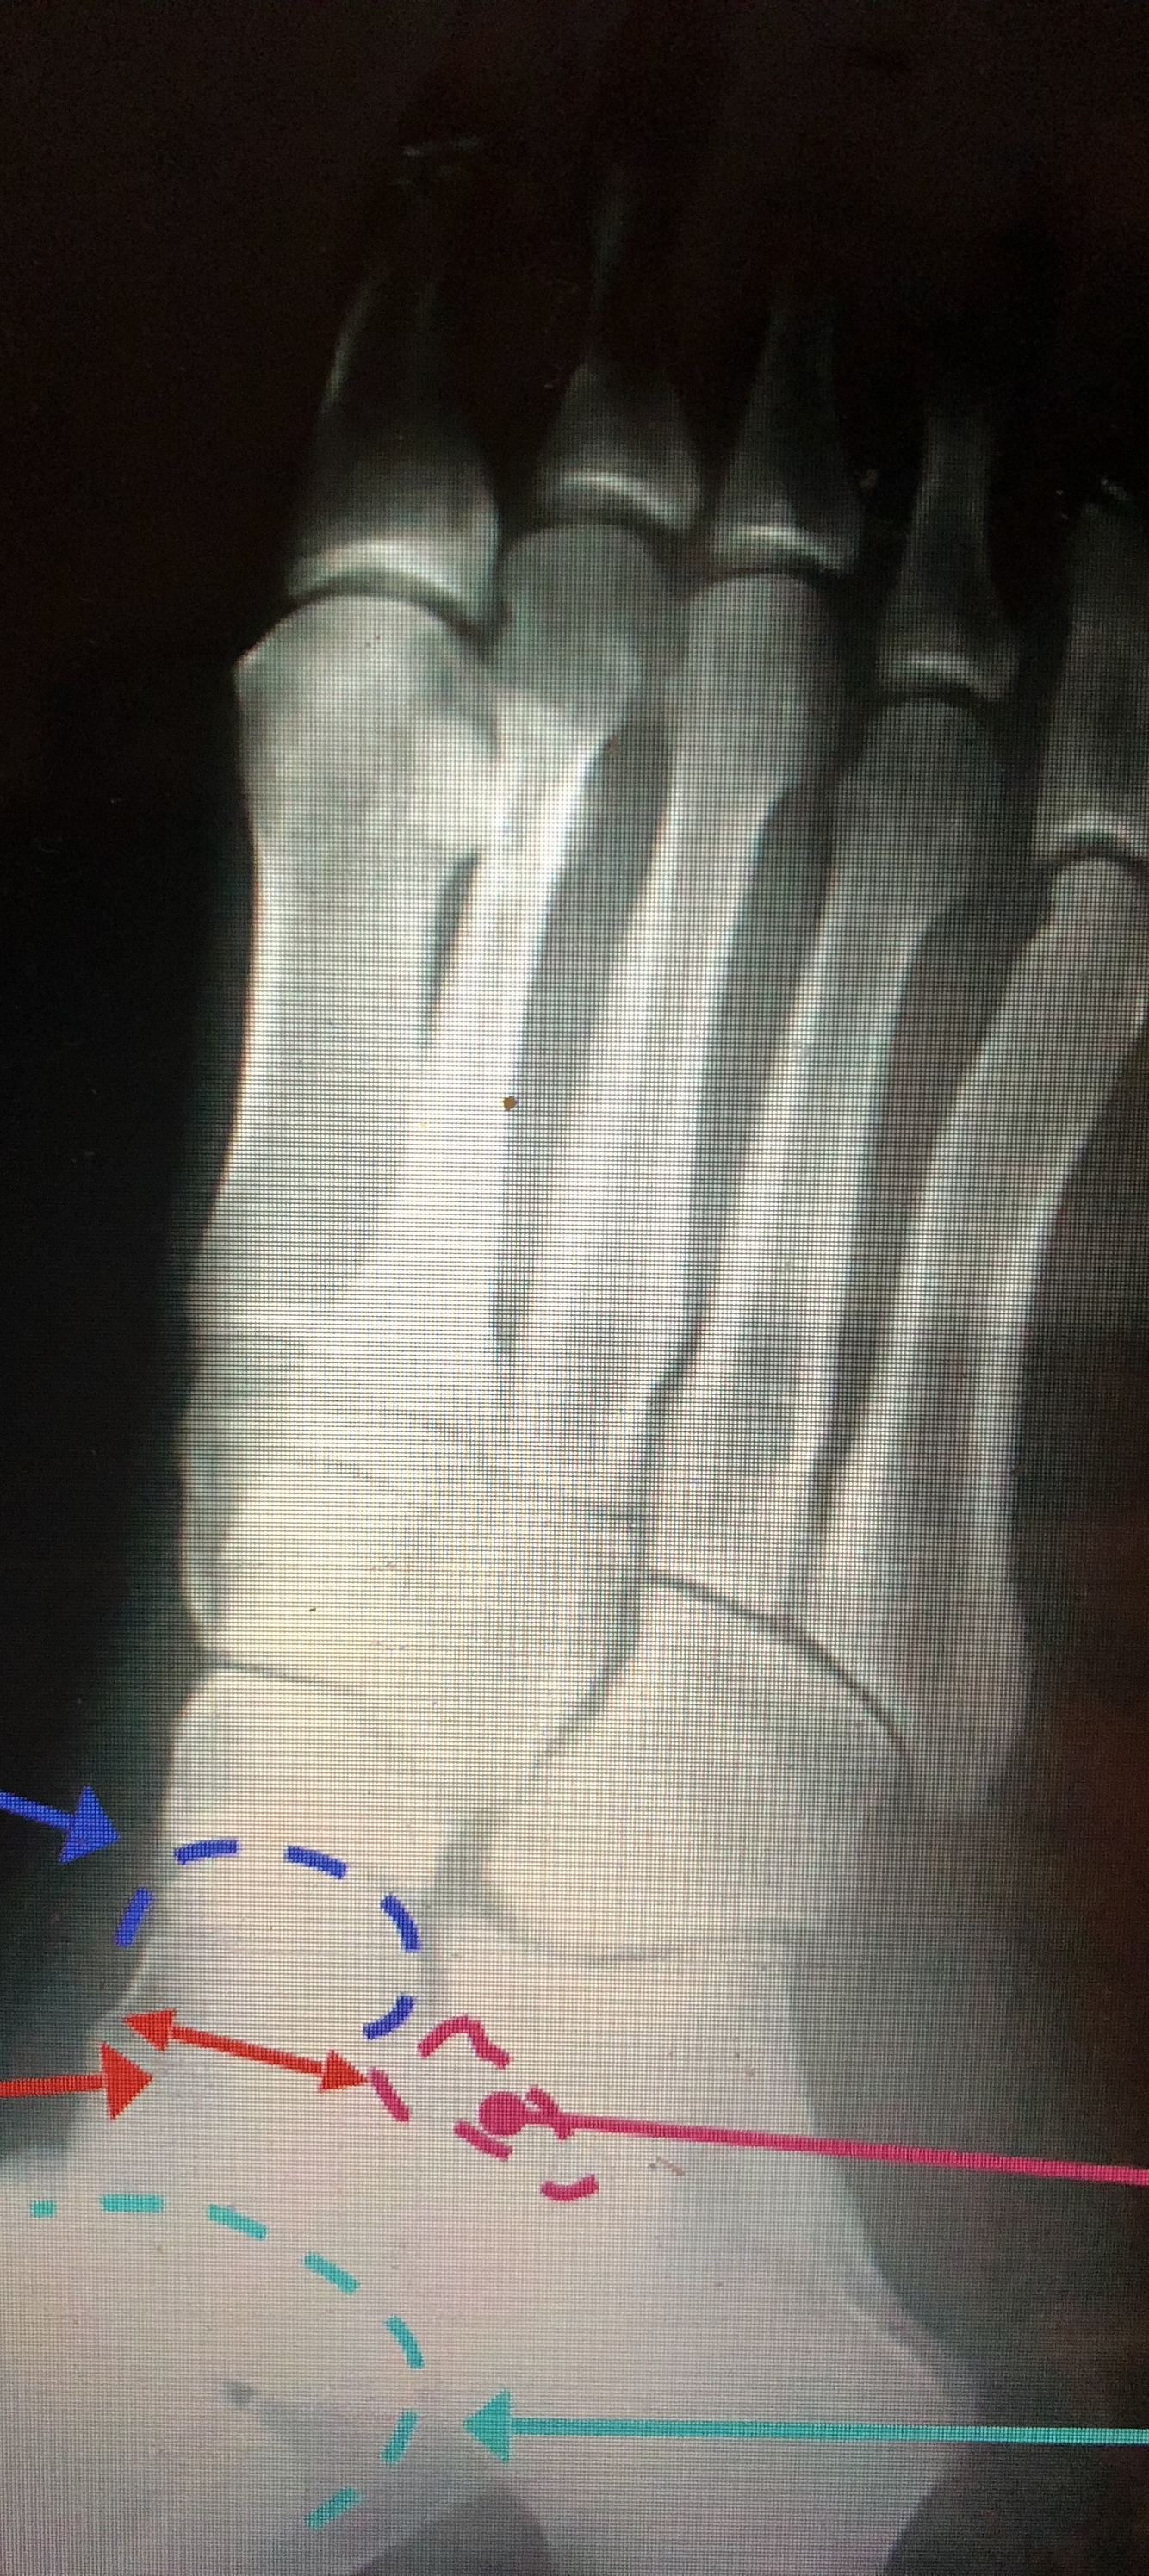

What bone is the dotted yellow line?

Cuboid

What bone is the purple dotted line?

navicular

What bone is the light green?

talus

What bone is the yellow solid dot?

Calcaneus

What bone is pink?

tibia

What bone is the dark green lines?

fibula

What is the dark blue?

Head of the Talus